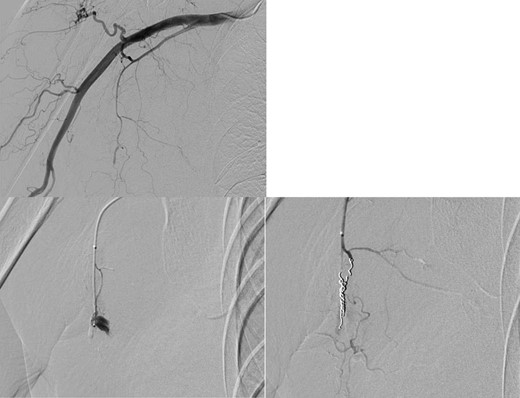

Four days later, the patient was hospitalized for rapidly worsening swelling and pain, and was readmitted with a diagnosis of rebleeding from the chest wall. Physical examination revealed a fist-sized subcutaneous mass on the right side of the chest, with severe pain. Laboratory data indicated anemia (Hb 7.8 g/dl) and no coagulation disorder: % prothrombin time (PT) 115.1%, prothrombin time-international normalized ratio (PT-INR) 0.93, and activated partial thromboplastin time 23.6 s. Computed tomography (CT) at the time of the first hemorrhage showed the hematoma on the right chest and anterior to the scapula (Fig. 2). Contrast-enhanced CT at the time of rebleeding showed an increase in hematoma and extravasation in the peripheral right lateral thoracic artery (Fig. 3). The patient was immediately treated with emergency angiography, which revealed active bleeding from a pseudoaneurysm of the right lateral thoracic artery. Thus, coil embolization was performed (Fig. 4). There were no TAE-related complications and the patient was discharged to home on the fifth hospital day. Oral clopidogrel was resumed and there has been no recurrence of bleeding.

Angiography showed active bleeding from a pseudoaneurysm of the right lateral thoracic artery. Coil embolization was performed.